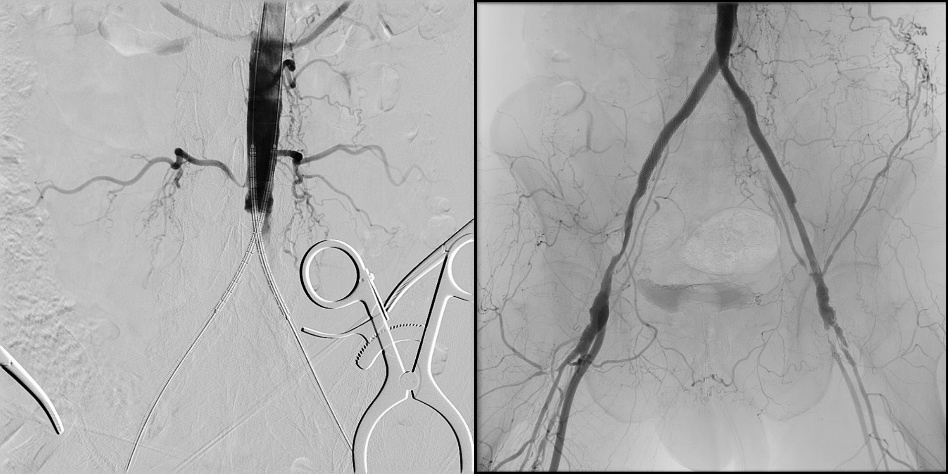

下肢血管における使用例を示す。術前CTAではAortic bifurcationからの完全閉塞となっていた(図5)。完全閉塞部分へのアプローチに対して難渋することが予測されたため、下肢血管解析結果を用いた3D Roadmap使用を検討した。AWVS7は下肢血管解析ソフトを用いることで自動的に血管、骨(術中3D Roadmapの位置合わせ用)を作成する(図6)。狭窄症例などでは自動作成された血管3Dを透視と重ねる3D Roadmapが治療サポートになるが、CTO症例ではワイヤーを進めるためのラインの有用性に着目し、CTO部分を含めた血管センターラインを作成した(図7)。血管センターラインはワイヤーを進める際のReferenceとして有用(図8)であり、3次元での位置情報を有したラインであるため、角度変更やFOV変更、テーブル移動にも追従する。また治療前のDSAでは表示されないTrue面を表示させることは、手技を進めていく中で有用なサポートになったと当院医師よりフィードバックがあった。3D Roadmapは術中にボリュームレンダリングの透過度変更や表示の有無、センターラインの表示の有無も変更可能である。CTO部分を通過させている場合にはセンターラインの表示、通過後のバルーン拡張やステント留置時にセンターラインではなく、ボリュームレンダリング表示による病変部の逆描出など場面に合わせた変更を可能としている。また任意5倍までのデジタルズーム表示機能もあり、今後の症例で使っていきたい。

IGS740_SendaiTokusyukai_05.jpg図5 DSA画像(左図は術前、右図は術後)